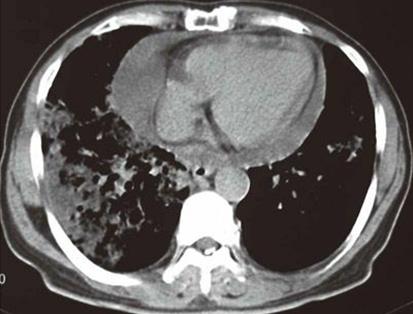

虽然肺癌伴随心包积液没有肺癌伴随胸腔积液那么常见,但也并不少见。人体的心包腔是包绕在心脏外的密闭腔隙,正常情况下存在20~40毫升的液体,对心脏的活动起到“润滑”的作用。当肺癌细胞通过肺部的血液循环进入心室腔,并通过冠状动脉被进一步运送到心脏表面,进而移行入心包腔(内行途径),或通过癌细胞向心包的直接侵犯(外行途径),或因肺癌肿块压迫了心包的淋巴回流(阻塞途径)等,都可造成肺癌性心包积液。

肺癌心包转移致心包积液